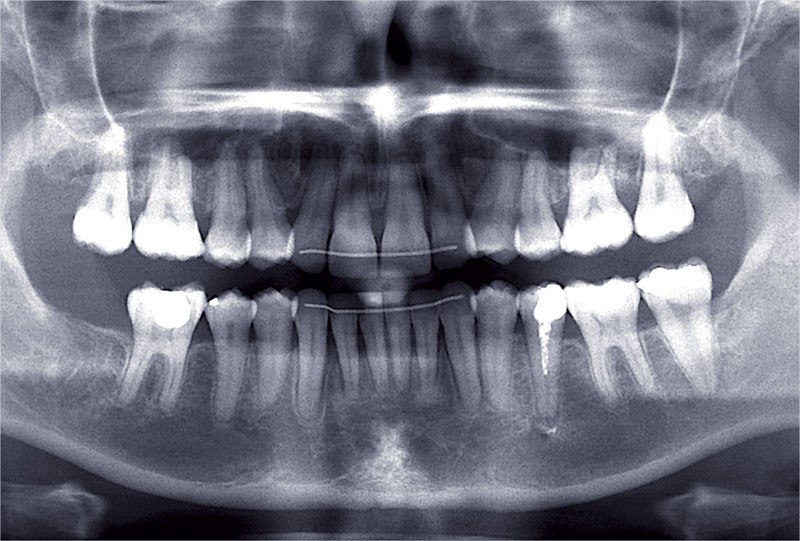

Conclusion

Les objectifs de traitement ont été remplis. Nous avons observé un excellent contrôle du torque et une absence de perte de l’occlusion postérieure grâce à la technique Insignia.